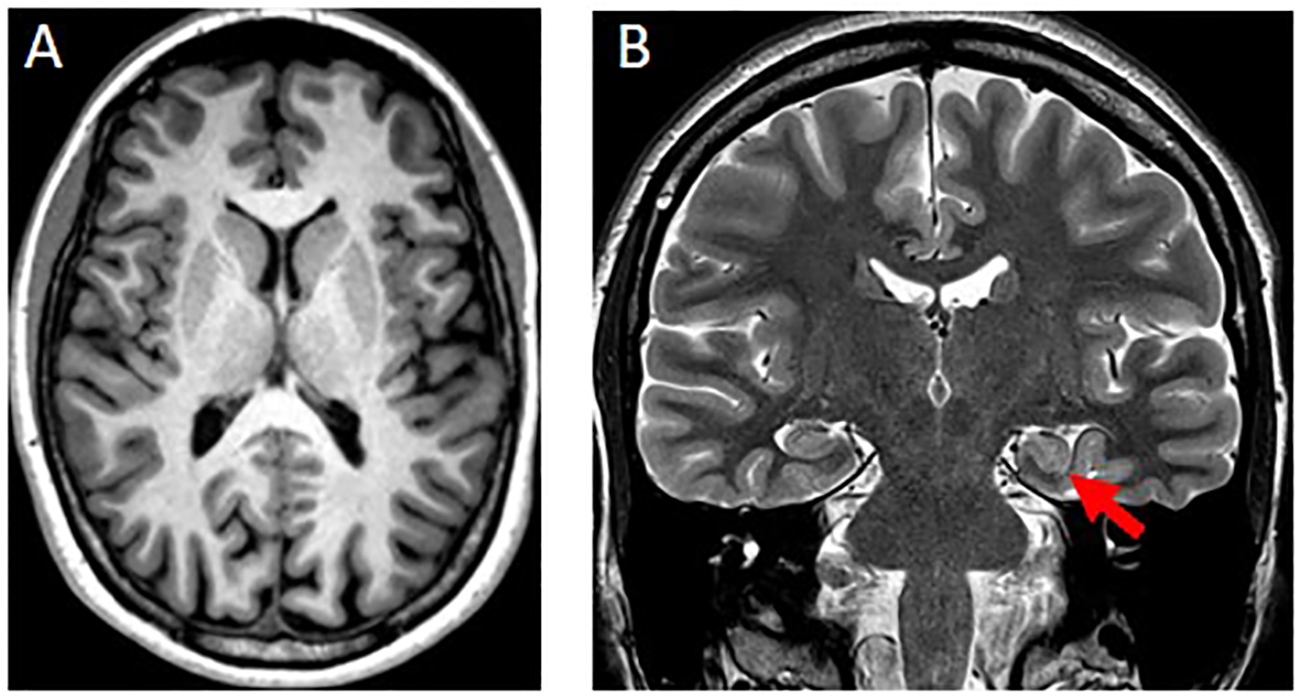

Brain-MRI showed a left-sided incomplete hippocampal inversion; no other brain parenchymal findings were noted (Figure 2).

Figure 2

(A) Axial T1w-MPRAGE image at the level of the basal ganglia was unremarkable. (B) Coronal T2w image showed a round-shaped of the hippocampal head on the left side (red arrow) with normal signal intensity, size and visualization of the internal structure. The left collateral sulcus is more vertical than the controlateral side. These findings are consistent with an incomplete hippocampal inversion.